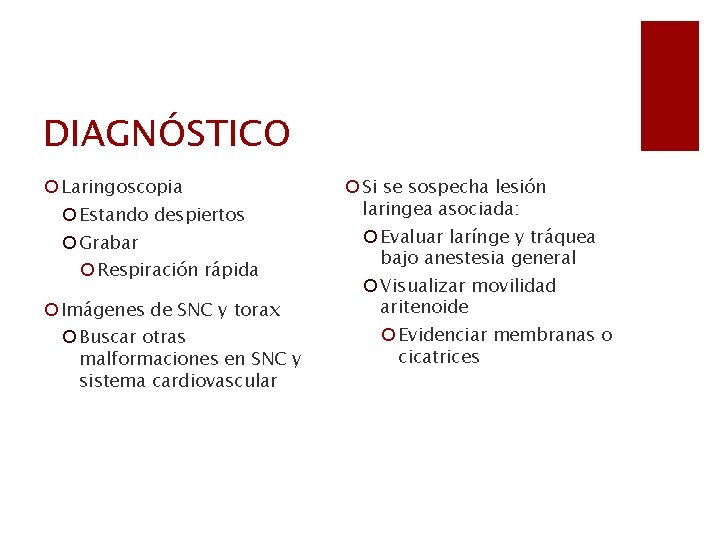

DIAGNÓSTICO ¡ Laringoscopia ¡ Estando despiertos ¡ Grabar ¡ Respiración rápida ¡ Imágenes de SNC y torax ¡ Buscar otras malformaciones en SNC y sistema cardiovascular ¡ Si se sospecha lesión laringea asociada: ¡ Evaluar larínge y tráquea bajo anestesia general ¡ Visualizar movilidad aritenoide ¡ Evidenciar membranas o cicatrices